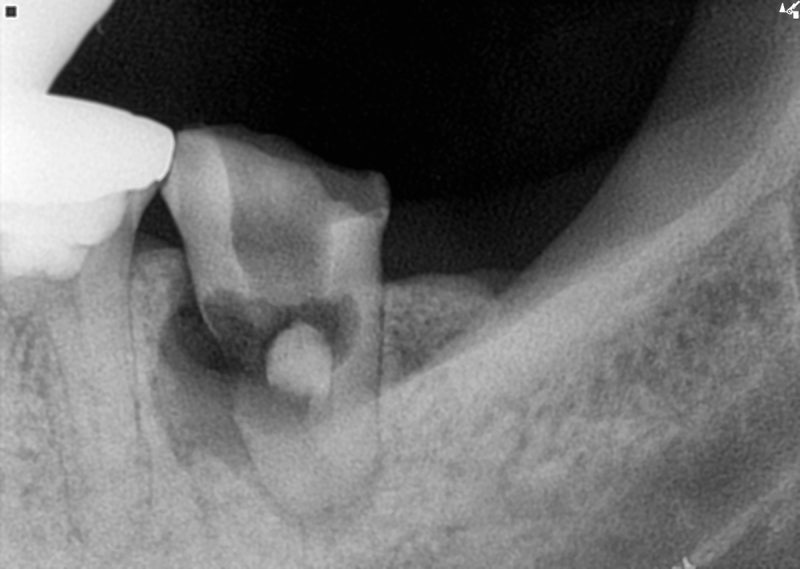

▲ 치료 후 파노라마 사진 설명 없이 비포 애프터 사진만 봐도 치과 치료를 많이 하셨고 임플란트가 필요한 치아가 많다는 것을 확인할 수 있습니다. 만성치주염이란 치아를 둘러싸고 있는 조직에 염증이 생겨 치아를 지탱하는 잇몸과 뼈가 파괴되는 질환입니다. 이러한 만성 치주염의 원인은 세균과 음식물 찌꺼기(박테리아 플라크, 세균 플라크)가 칼슘과 결합하여 치아가 나면서 치석을 형성하고 치주낭을 형성하며 치조골을 파괴하여 잇몸 질환의 증상을 유발하기 때문입니다. 습관은 물론 전신질환과 불균형, 당뇨, 심혈관질환, 임신, 영양이상 등도 원인이 될 수 있습니다. ▲ 발치 후 뼈이식이 필요할 때! 다양한 이유로 발치를 해야 하는 경우도 있고, 뼈이식을 해야 하는 경우도 있고, 발치가 필요하지 않은 경우도 있습니다. 치과용 임플란트를 식립하기 위해서는 식립된 치은의 상태, 즉 주변 조직에 남아있는 뼈의 양이 임플란트의 직경과 높이를 고려하여 치은골의 폭과 길이가 충분히 확보되어야 합니다. 치아의 경우 더 많은 뼈 이식이 필요합니다. ▲ 발치 후 뼈이식이 이렇게 염증이 심한 상태가 되면 염증이 치아뿐만 아니라 주변 치아까지 번지게 됩니다. 골이식은 멸균 후 비감염성으로 진행하였으며, 골이식은 물방울 레이저로 진행하였다. ▲ 물방울 레이저 골이식 물방울 레이저는 잇몸 주변 조직에 대한 살균 효과가 뛰어나 시술 시 출혈이 거의 없고 시술 후 부기가 거의 없다. 레이저에 비해 큰 이점을 제공하는 고가의 의료 기기입니다. 치료가 잘 되었습니다. 염증이 심한 잇몸을 무통 레이저로 치료한 사례! 안녕하세요 파주운정 아픈치과의원입니다. 파주운정 안아픈치과의원 일산탑치과 원장입니다. 치과에서 레이저 치료? 궁금하신 분들을 위해… blog.naver.com 골이식 유합술은 부족한 부분을 골이식재로 보강한 후 보통 3~5개월이 소요됩니다. ), 임플란트 고정물을 배치합니다. ▲ 임플란트 픽스쳐 식립 임플란트 식립이 불합리한 경우 픽스쳐, 즉 임플란트의 고정체가 제대로 고정되지 않아 시간과 비용이 더 많이 들 수 있다. 따라서 다음 치료를 진행하기 전에 충분한 치조골을 준비하는 것이 중요합니다. ▲ 임플란트 식립 5개월 후 모습 임플란트 식립 후 치은골과 픽스츄어가 잘 결합되기까지 시간이 걸립니다. 이 환자를 예로 들면 약 5개월이 소요되며 임플란트 고정값은 다음 값을 사용하여 계산되며 수치로 표시됩니다. ▲ ISQ 임플란트 안정성 견적을 측정할 때 70 이상의 값을 얻으면 치유가 제거되고 수복물이 위에 놓일 수 있습니다. Torque 측정법이 있지만 이 방법들은 정확하지 않고 식립된 인공치아에 악영향을 끼친다 ▲ 보철물이 완성된 후 이렇게 보철물을 들어올리면 성공적으로 임플란트 치료가 끝난다. 그러나 한 가지 기억해야 할 것이 있습니다. 수술 후 관리가 중요합니다. 임플란트 자체에는 신경이 없기 때문에 통증을 느끼지 못할 수도 있지만, 임플란트 주위나 치아와 임플란트 사이의 공간에 플라그가 침착되어 잇몸에 염증이 생겨 임플란트 주위염을 유발할 수 있습니다. 이 점은 매우 중요합니다! 임플란트에 염증이 생길까요? 임플란트주위염 일산서구치과의원 안녕하세요. 일산서구치과병원 일산탑치과병원 원장입니다. 임플란트는 상실된 치아를 대신할 수 있는 좋은 치료법… blog.naver.com 임플란트 주변에 염증이 생겨도 스스로 치유되지 않아 자각하기 쉽고 치아를 보호하는 치주인대가 없기 때문에 더욱 주의가 필요합니다. 치아 조심해서 다루십시오. 또한 임플란트를 식립한 치과의사가 정기적으로 체크인하는 것을 기억하는 것이 중요합니다.물방울 레이저